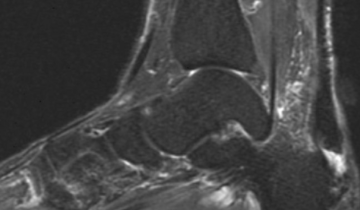

The Extremities

Differential Diagnosis